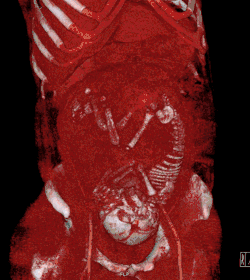

| Tomografia computadorizada | |

| Cabeça ou pescoço | 1.0 - 10[1] |

| Tórax, incluindo angiografia pulmonar por TC | 0.01 - 0.66[1] |

| Pelve limitada (corte axial único pelos cabeças femorais) | < 1[1] |

| Abdome | 1.3 - 35[1] |

| Pelve | 10 - 50[1] |

Câncer de mama induzido por radiação

O risco para a mãe de desenvolver posteriormente câncer de mama induzido por radiação parece ser particularmente alto para doses recebidas durante a gestação.[6]

Esse é um fator importante, por exemplo, ao decidir entre cintilografia de ventilação/perfusão (V/Q scan) ou angiografia pulmonar por TC (CTPA) em gestantes com suspeita de embolia pulmonar. A cintilografia confere maior dose de radiação ao feto, enquanto a CTPA confere dose muito maior às mamas da mãe. Uma revisão do Reino Unido em 2005 considerou a CTPA geralmente preferível nesses casos, devido à maior sensibilidade e especificidade e ao custo relativamente baixo.[7]